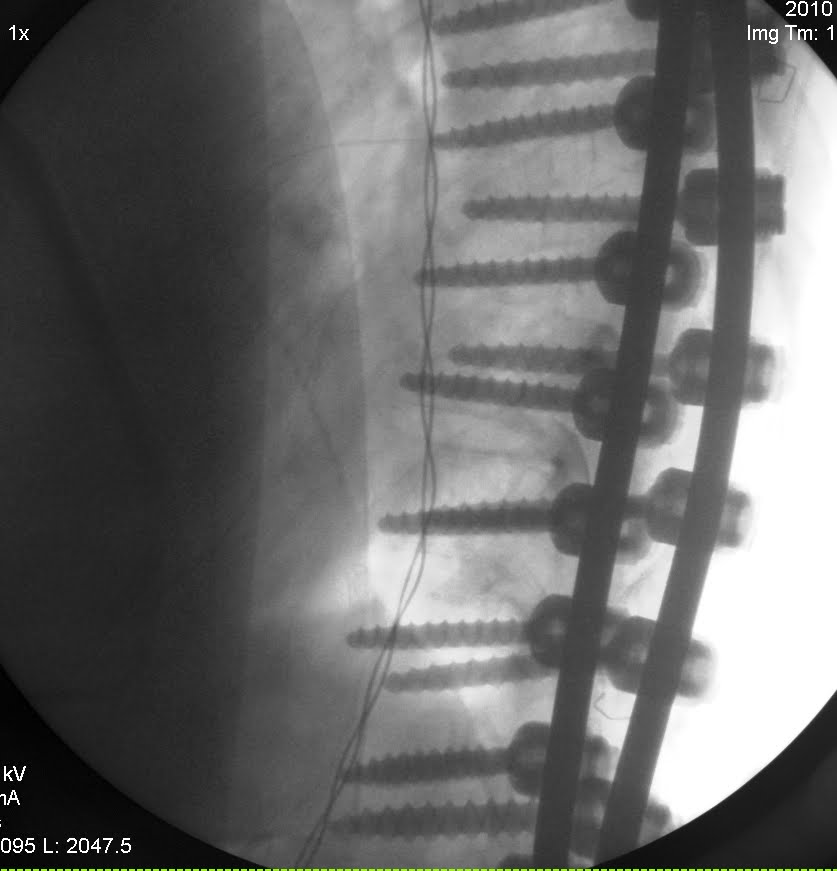

Our daughter underwent T2-L3 posterior spinal fusion on May 20, 2010 with the diagnosis of Type 5 Lenke scoliosis (severe thoracic curve) at Seattle Children Hospital by Dr Theodore A Wagner. Our daughter was brought to the operating room and given a general anesthetic at 13:00 o’clock, operation time took six hours, incision started on 14:15 and the procedure completed on 20:15 but our daughter was taken to the patient room at around 23:00. The next day at 10:00 a.m. our daughter had been trained to sit on the edge of the bed for about 5 minutes, on day two had got out of bed to sit in a chair for about 45 minutes, on day three she already been able to get up and down the bed for 3 times and sat in a chair for several hours, day 4 had learned to walk in the pathway outside the patient room and day five had been discharged from the hospital, day 7 was able to walk about 50 meters outside apartment and lie to the right and left side of her sleeping position without assistance and most amazing things that on day 14 after the spinal fusion my daughter was not taking any pain medicines nor any drug and she could walk for about 2.2 km (1.4 Miles). As a matter of fact our daughter spinal fusion is a very big and complicated surgery procedures, spinal fixation hardware has been placed from upper thoracic to lumbar spine, 25 pieces polyaxial titanium screws that were 35 mm long each were tapped to her spine. Those screws are tied together with an alloy rod and the cartilage and joints between the vertebrae was removed and placed by bone graft (extra bone) from the bone bank. Dr. Wagner said that the parts of the spine that are fused will stop growing but the child still growing from the other parts that are not fused, meaning that she still can growth, able to do all of the sport she likes, bending her body, able to be pregnant and delivery children. Those are really very amazing, that shows to us how wonderful that God can create such people that can do all of this.